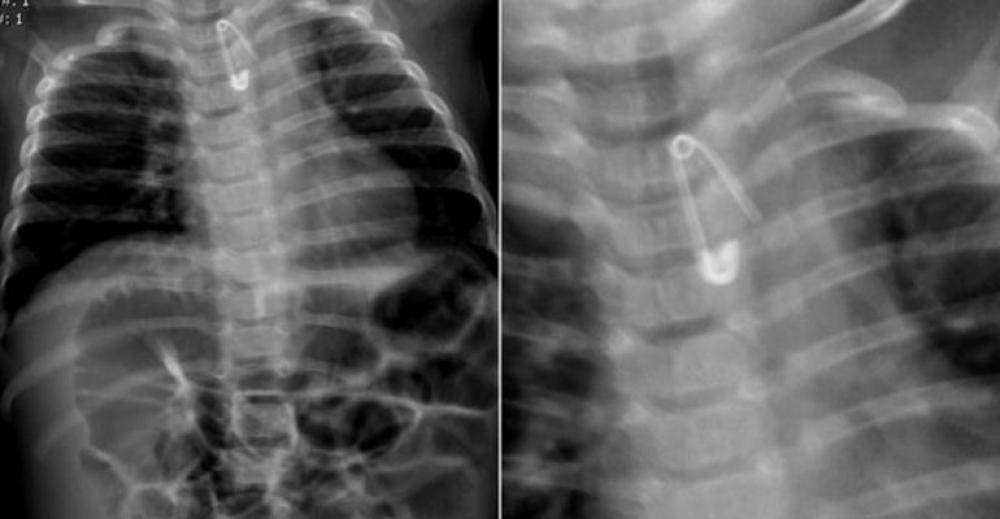

Pomocy w krotoszyńskim szpitalu szukali rodzice 6-miesięcznego dziecka. Malec połknął bowiem 2-centymetrową agrafkę. Rozwarta zapinka  ostrzem skierowanym ku dołowi – uwięzła w przełyku chłopczyka – co wskazywało zdjęcie rentgenowskie.

Lekarka pełniąca dyżur na SOR-ze poleciała rodzicom udać się do szpitala w Ostrowie Wielkopolskim – oddalonej od naszego miasta 30 km. I choć w tym czasie na stanie były dwie karetki, kazała im jechać własnym samochodem. Ci oczywiście natychmiast ruszyli w drogę. W międzyczasie malec zaczął się krztusić. W Biadkach zauważyli policyjny patrol. Nie zwlekając, poprosili mundurowych o pomoc  w dotarciu do celu. I tak pod eskortą radiowozów z Krotoszyna i Ostrowa na sygnałach udało się dotrzeć na miejsce. Ostatecznie dziecko już karetką zostało przetransportowane do Wrocławia, gdzie podczas zabiegu laparoskopem lekarze wyjęli agrafkę wczepioną w struktury przełyku maluszka.